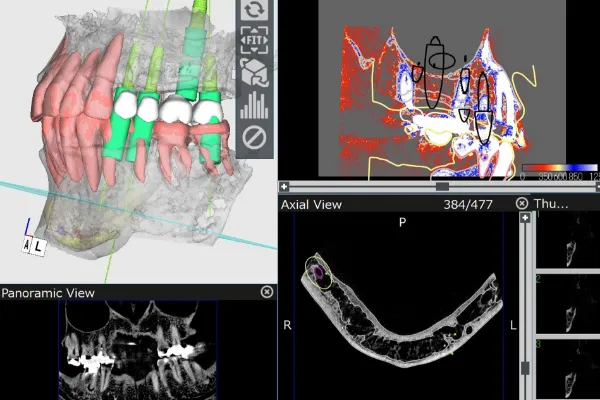

患者様のお口の中を3Dデータ化し

インプラントの埋入位置を正確に分析・診断。

CTスキャンを活用し、

患者様の口腔内を

3Dデータで精密に解析

加藤総合歯科・矯正歯科では、CTスキャンにより口腔内を3D化し、

コンピューターシステム「ビオナ」で歯の状態を詳しく解析します。

専門医とコンピュータ技術が連携し、インプラントの位置や角度をミリ単位で正確に決定、手術時のリスクを最小限に抑えます。

精密な手術計画と

シミュレーションを通じて、

治療の負担を最小限に抑えます。

インプラント治療では、患者様の体にかかる負担を軽減するため、入念な治療計画を立ててから実施します。治療計画患者様に十分に説明し、ご理解とご納得を得た上でい進めていきます

さらに、インプラント埋入位置を正確に決定するため、サージカルガイドを使用し、歯ぐきをほとんど切開せずに手術を行うことで、術後の腫れや痛みを最小限に抑えます。

CTスキャンを活用して口腔内の立体的なモデルを作成し、歯の状態を正確に分析。その結果を基に精密なインプラント治療計画を立てます。

インプラント手術前に精密な検査を行い、従来の歯科用レントゲンだけでなく、CTスキャンで骨の状態や神経の走行を把握し、さらにお口の型取りで歯肉の状態も調べます。これにより、治療計画をコンピューター上でシミュレーションし、安全性を確保した治療を行っていますので、安心してお任せください。

CTスキャンを使用して精密なシミュレーションを行い、骨の状態や上顎洞の位置を正確に確認していますので、このようなトラブルは発生しません。

CTスキャンを使用して精密なシミュレーションを行い、骨の状態や上顎洞の位置を正確に確認していますので、このようなトラブルは発生しません。